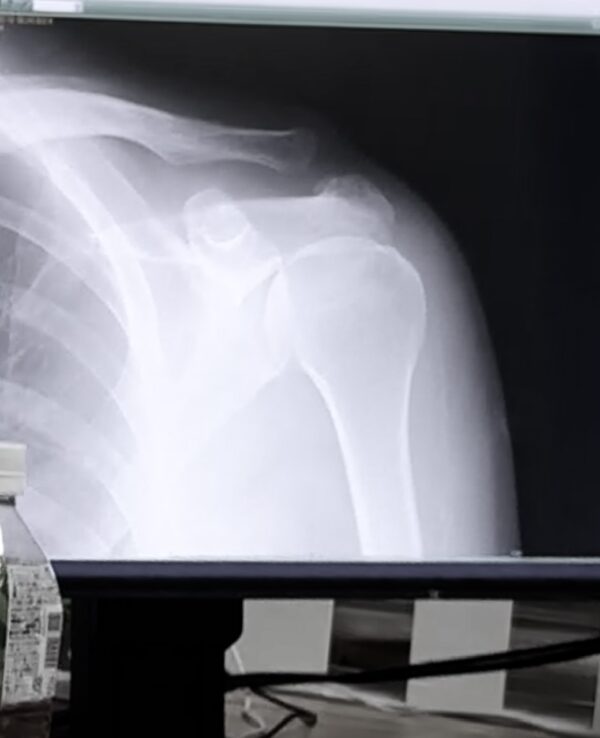

一年前に懸垂

で痛めた左肩甲骨

がまた痛み出したので病院へ

肩甲骨osatokyo

(異常なし)